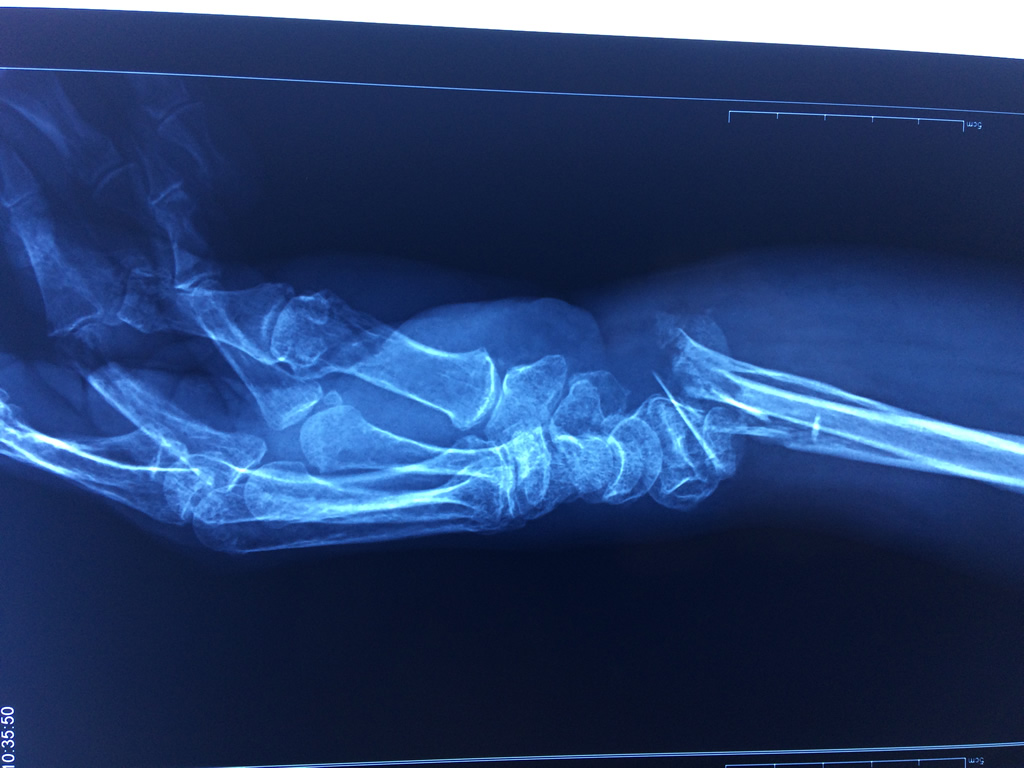

Cirugía de Fémur - Cirugías de Muñecas y Manos

Los procedimientos más comunes en cirugía de la mano son aquellos destinados a reparar traumatismos, incluyendo lesiones de tendones, nervios, vasos sanguíneos, y articulaciones; huesos fracturados; y quemaduras, cortes, y otros daños de la piel.